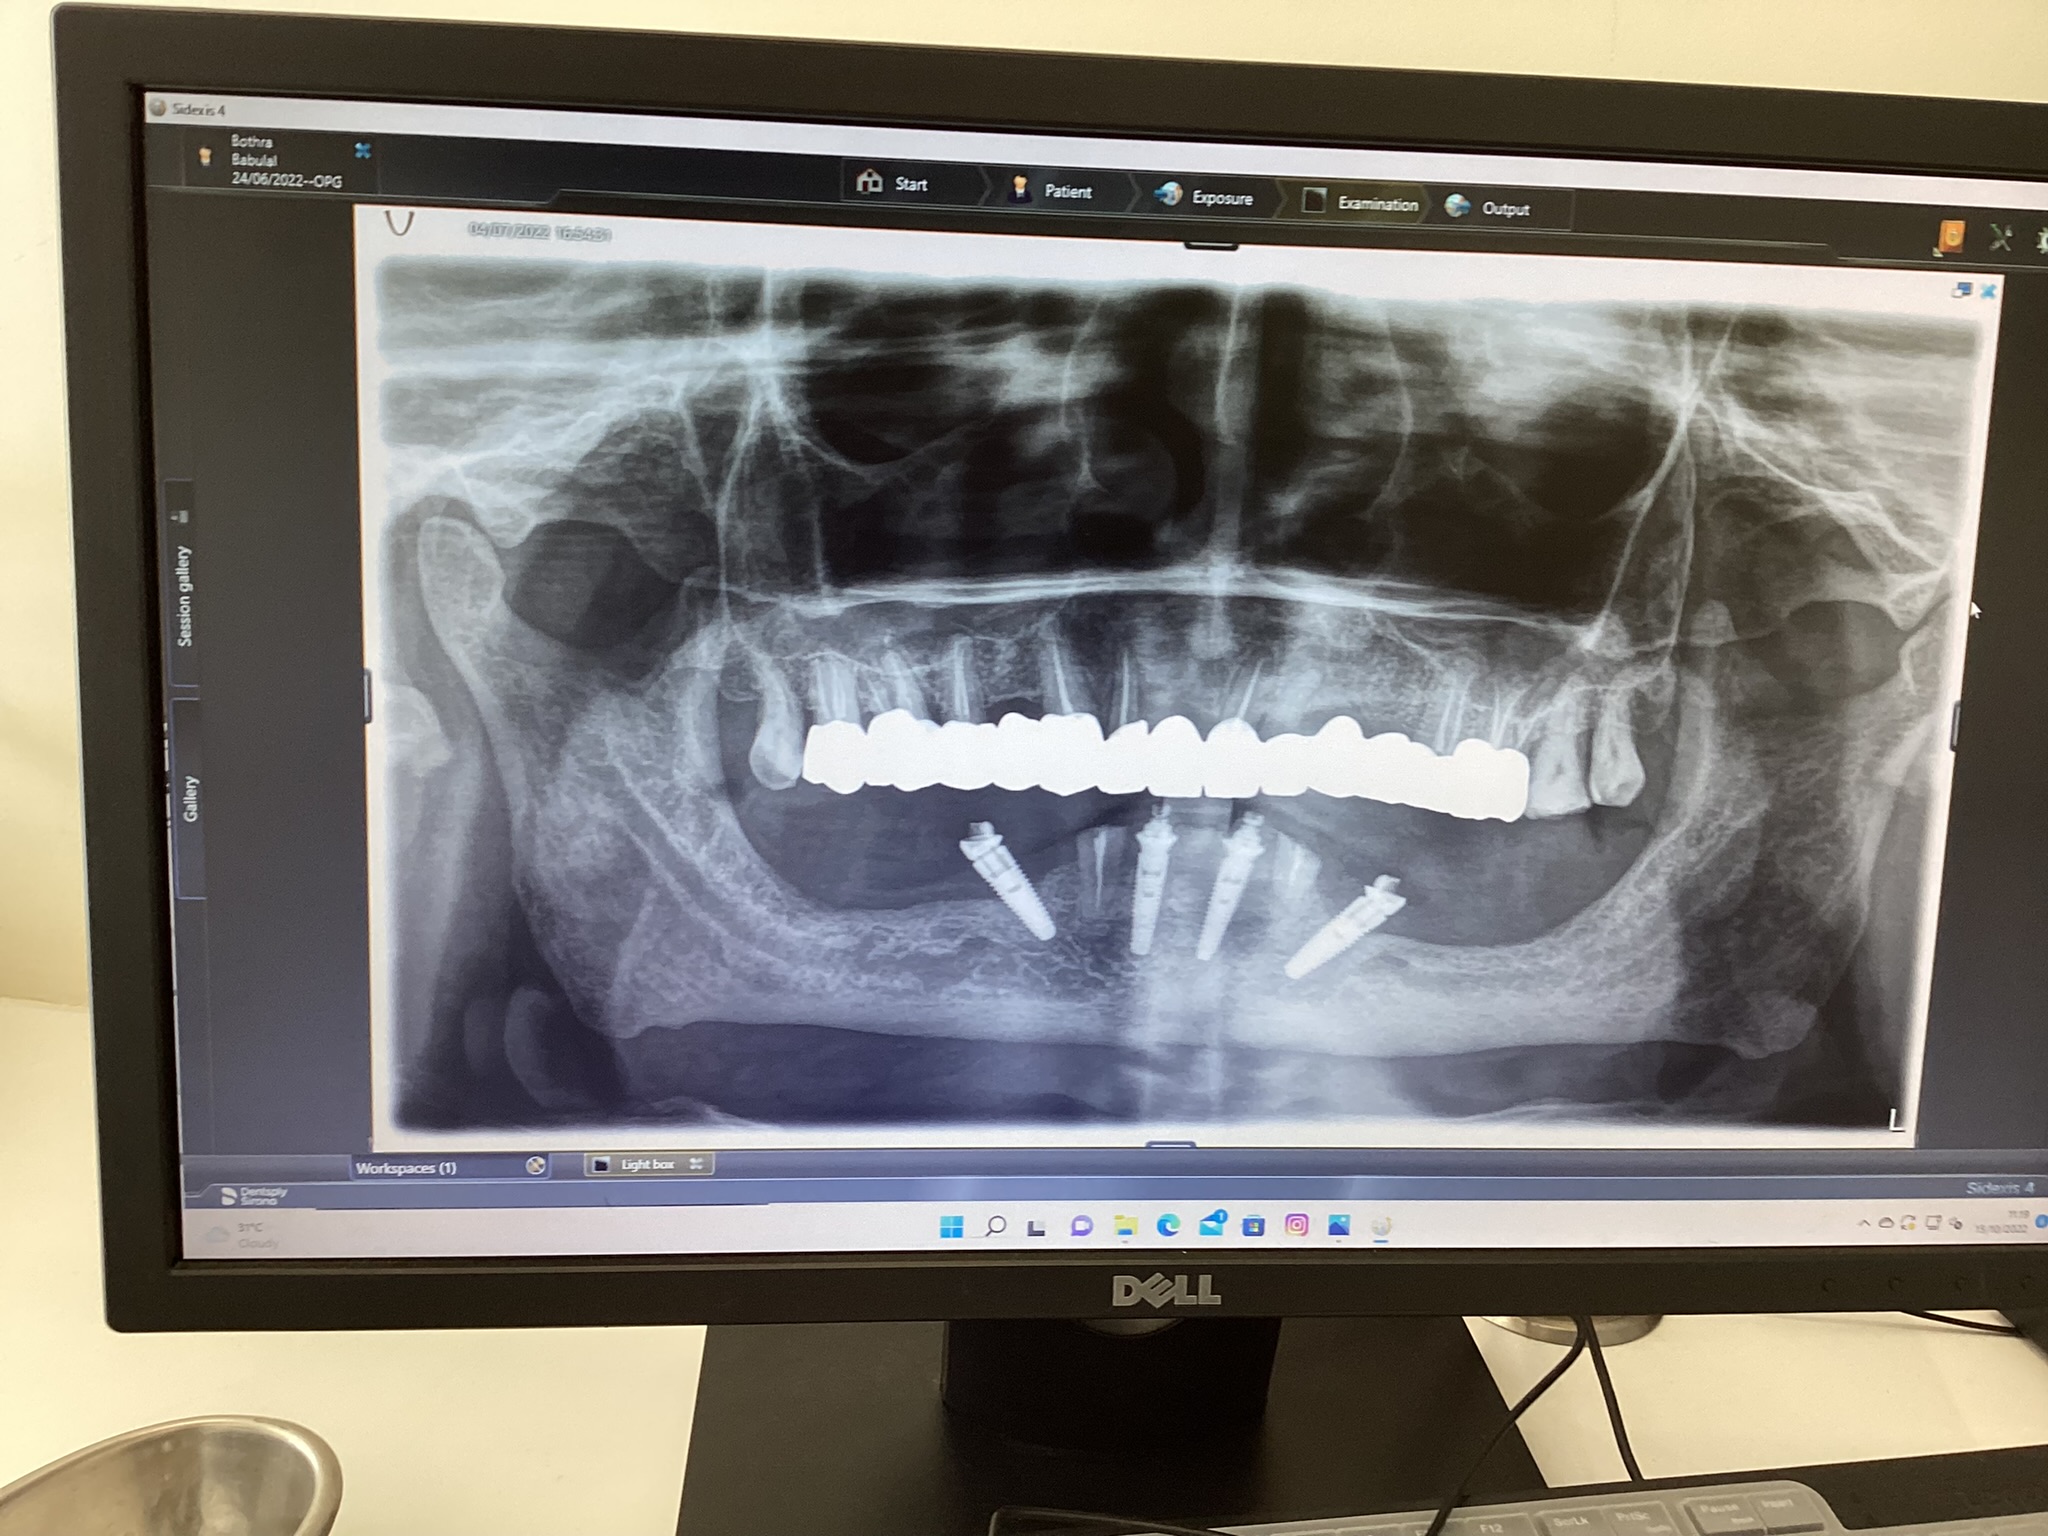

If you are looking for a permanent solution for your missing teeth, dental implants can be the right choice. Kolkata metal posts enter specific spaces in your jaw during surgery. Your bone tissue grows through tiny spaces on each post surface. Natural healing joins metal and bone into single units. This fusion creates firm foundations for teeth that work like natural ones.